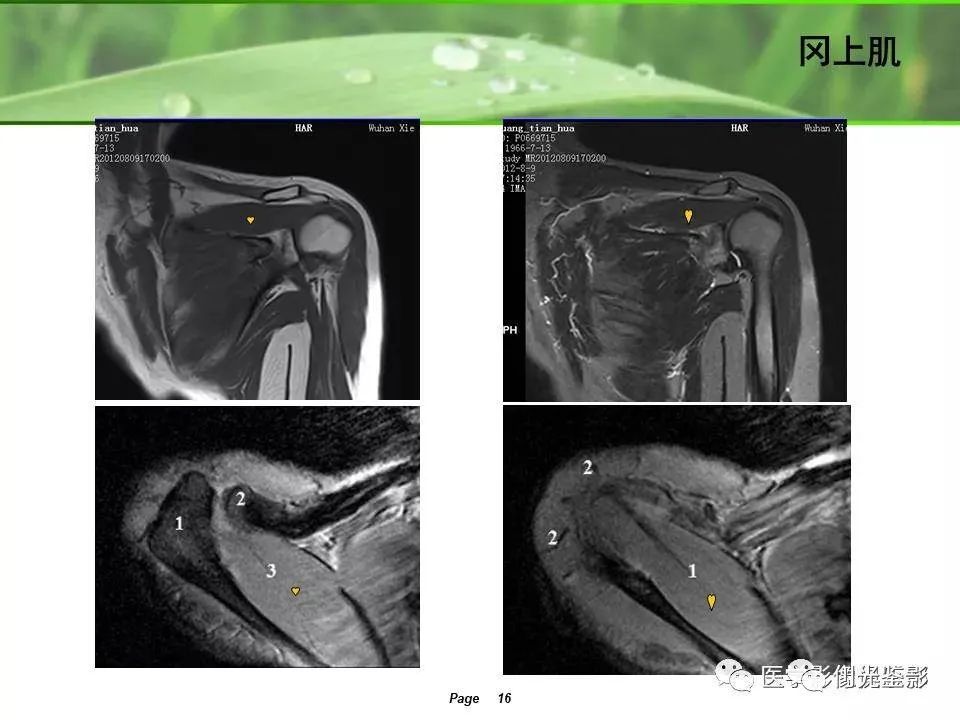

肩关节MRI检查扫描平面

1、斜冠状位:平行于冈上肌腱长轴,主要评估冈上肌。

正常肩袖的MRI表现

各个序列肩袖均表现为均匀的低信号,是肌腱的延续。

2、正常的腱性纤维条影

冈上肌的腱性纤维在MRI上表现为长条状低信号影,不要认为是撕裂。